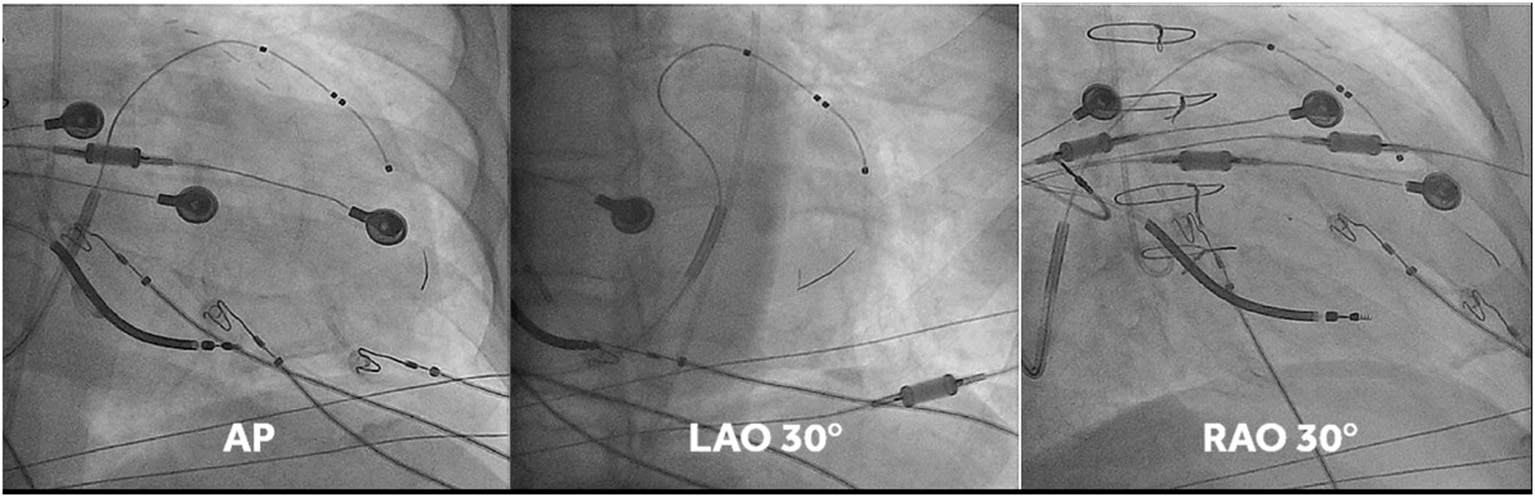

This was undertaken using standard transvenous techniques with cephalic, axillary or subclavian access. Right atrial and right ventricular leads were first deployed into typical locations (preferred right atrium appendage if possibly and right ventricular apex or low septum, respectively), followed by deployment of a quadripolar LV lead within the vein chosen by implanters, who were instructed to deploy the LV lead tip as apical as possible within the vein of choice (an example of lead placement is shown in Figure 1). If the apex could not be reached with a transvenous LV lead, a 0.14” pacing wire (VisionWire, Biotronik, Berlin) was used for apical pacing. Apical position was defined by 30° RAO fluoroscopy as the lowest quartile in the longitudinal direction and was achieved in 100% of the patients. Acceptable LV lead position was either lateral or posterolateral (Figure 1).

Figure 1

Fluoro-images at AP, LAO 30° and RAO 30° displaying position of the different CRT leads. Note that in this case the vision wire administered through the lumen of the quadripolar was used to obtain true apical position. MPP was delivered on the vision wire, and on the distal and most proximal electrodes of the short bipole of the quadripolar lead.